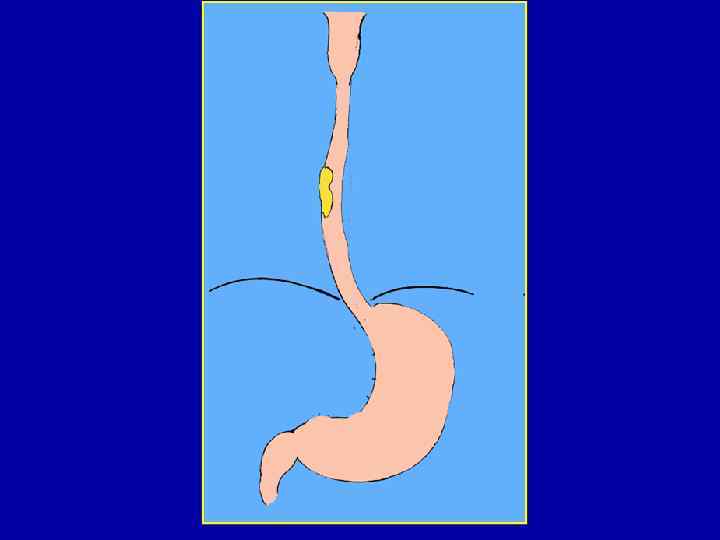

Больная К. , 56 л. Ds: кардиоспазм IV стадии 10. 09. 03 – экстирпация пищевода с одномоментной пластикой желудочной трубкой

Экстирпация пищевода 35 см